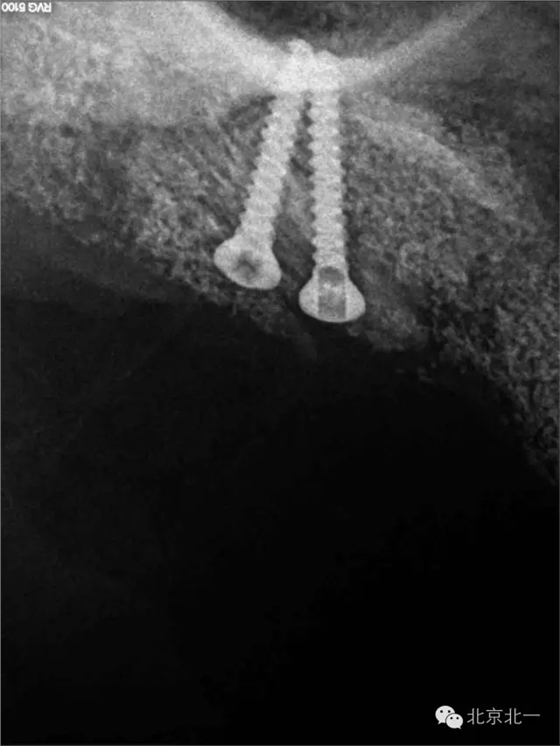

圖二十三:種植后當天全景片。